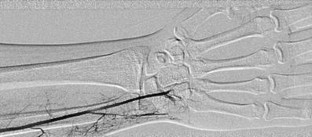

Fig. 4